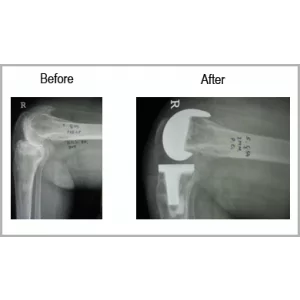

A female 54 year old who is known case of RA had severe right knee pain. She had not moved out of her house for more than a year. She had fracture of thigh bone before 2 years which was treated with plaster. She also had kidney infection and deep venous thrombosis. After completion of treatment for kidney and deep venous thrombosis, she was advised right total knee replacement.

After her successful right Total knee replacement, she is back to her normal activities without any kind of support. She is able to move on a two wheeler.